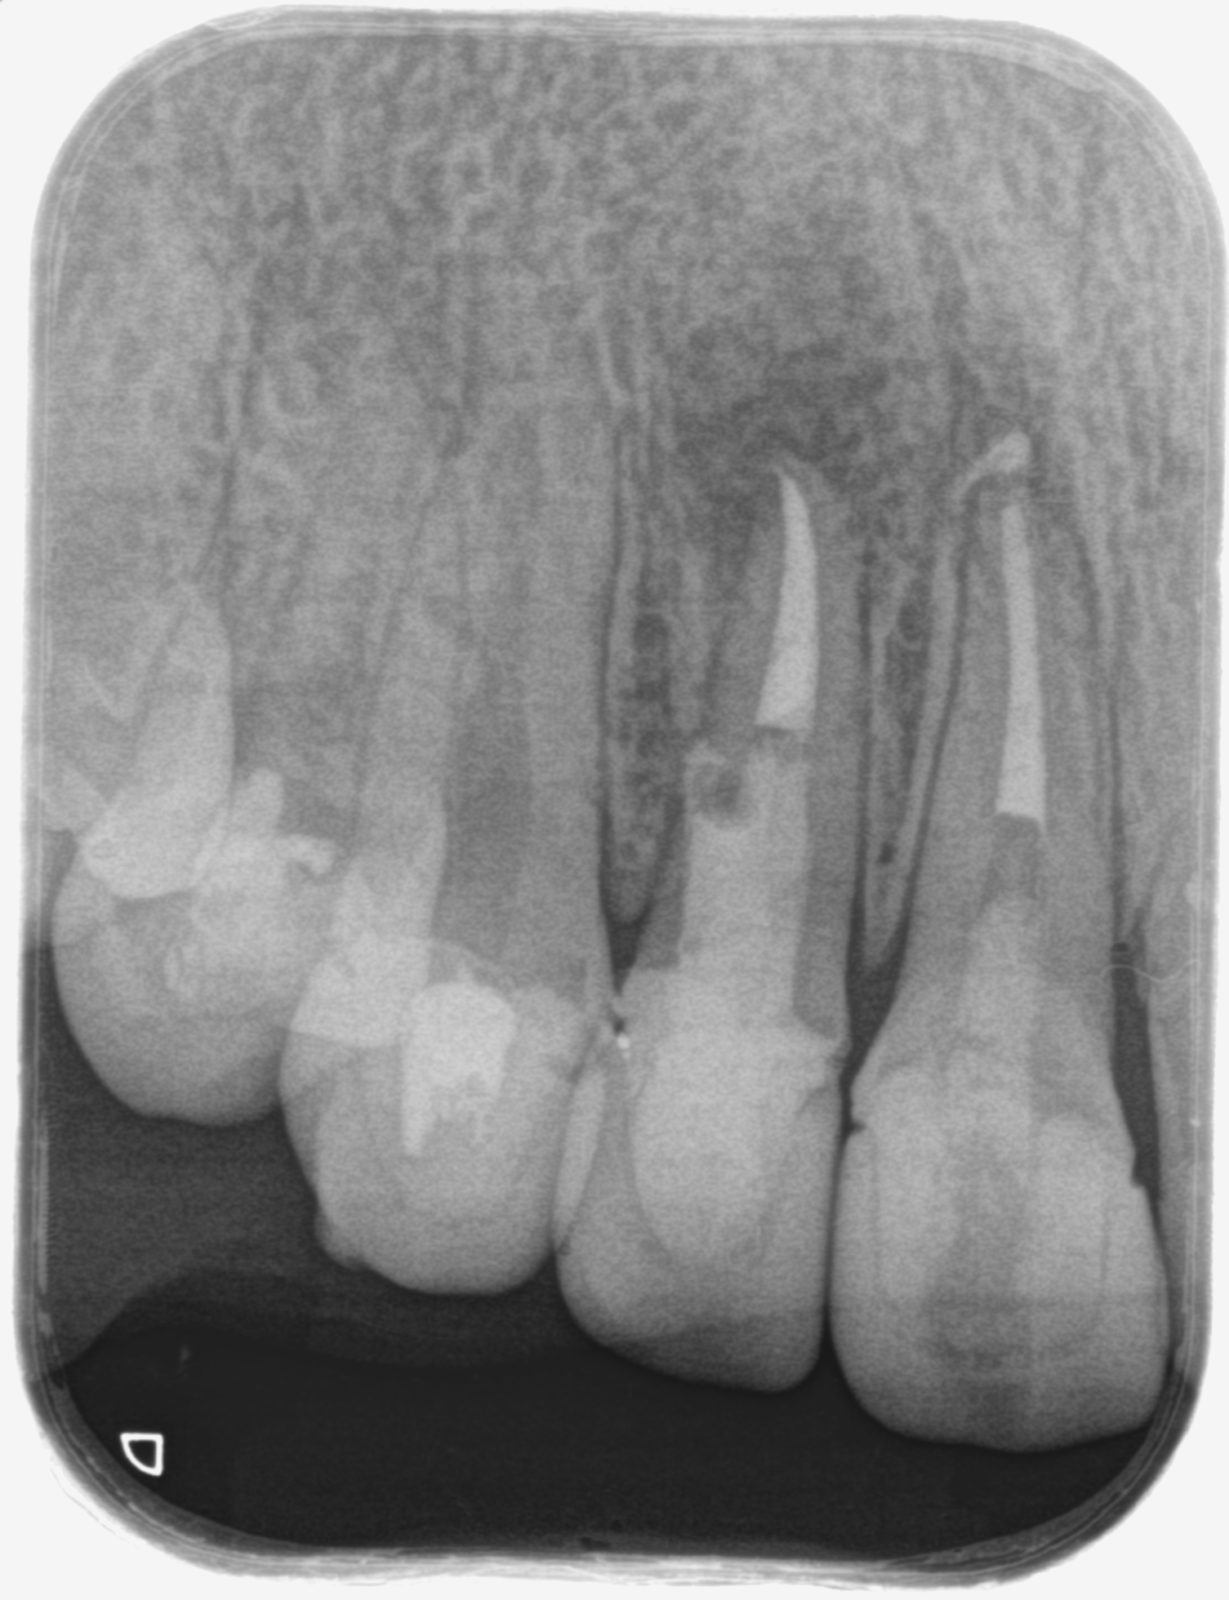

• 治療前

• 治療後

主訴他院で治療した右上の前歯にズーンとした違和感がある たまに噛むと痛い

どのように治療したのかの具体的な説明当院の歯内治療専門医による歯根端切除術(外科的歯内療法)。歯根端を切除、逆根管形成後MTAを充填。

治療期間治療開始からは一回の来院のみ、一時間半ほど。

治療費14.3万円 (当医院で二年以内に自費根管治療している場合は半額)

その治療をすることで起こり得るリスク歯根が短くなることにより動揺が出る恐れがある